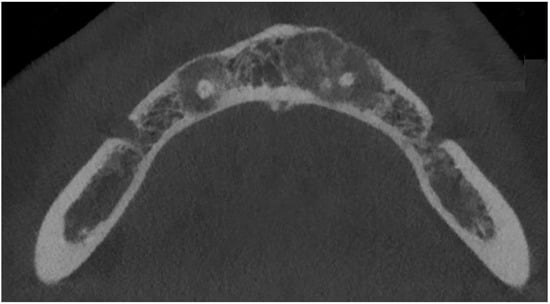

- mixed radiolucent/radiopaque lesion (depending on the stage of COD maturation), Figure 1.

- radiolucent with/without radio-opacities with thin radiolucent rim, Figure 2

- associated with anterior/posterior teeth (Figure 2)